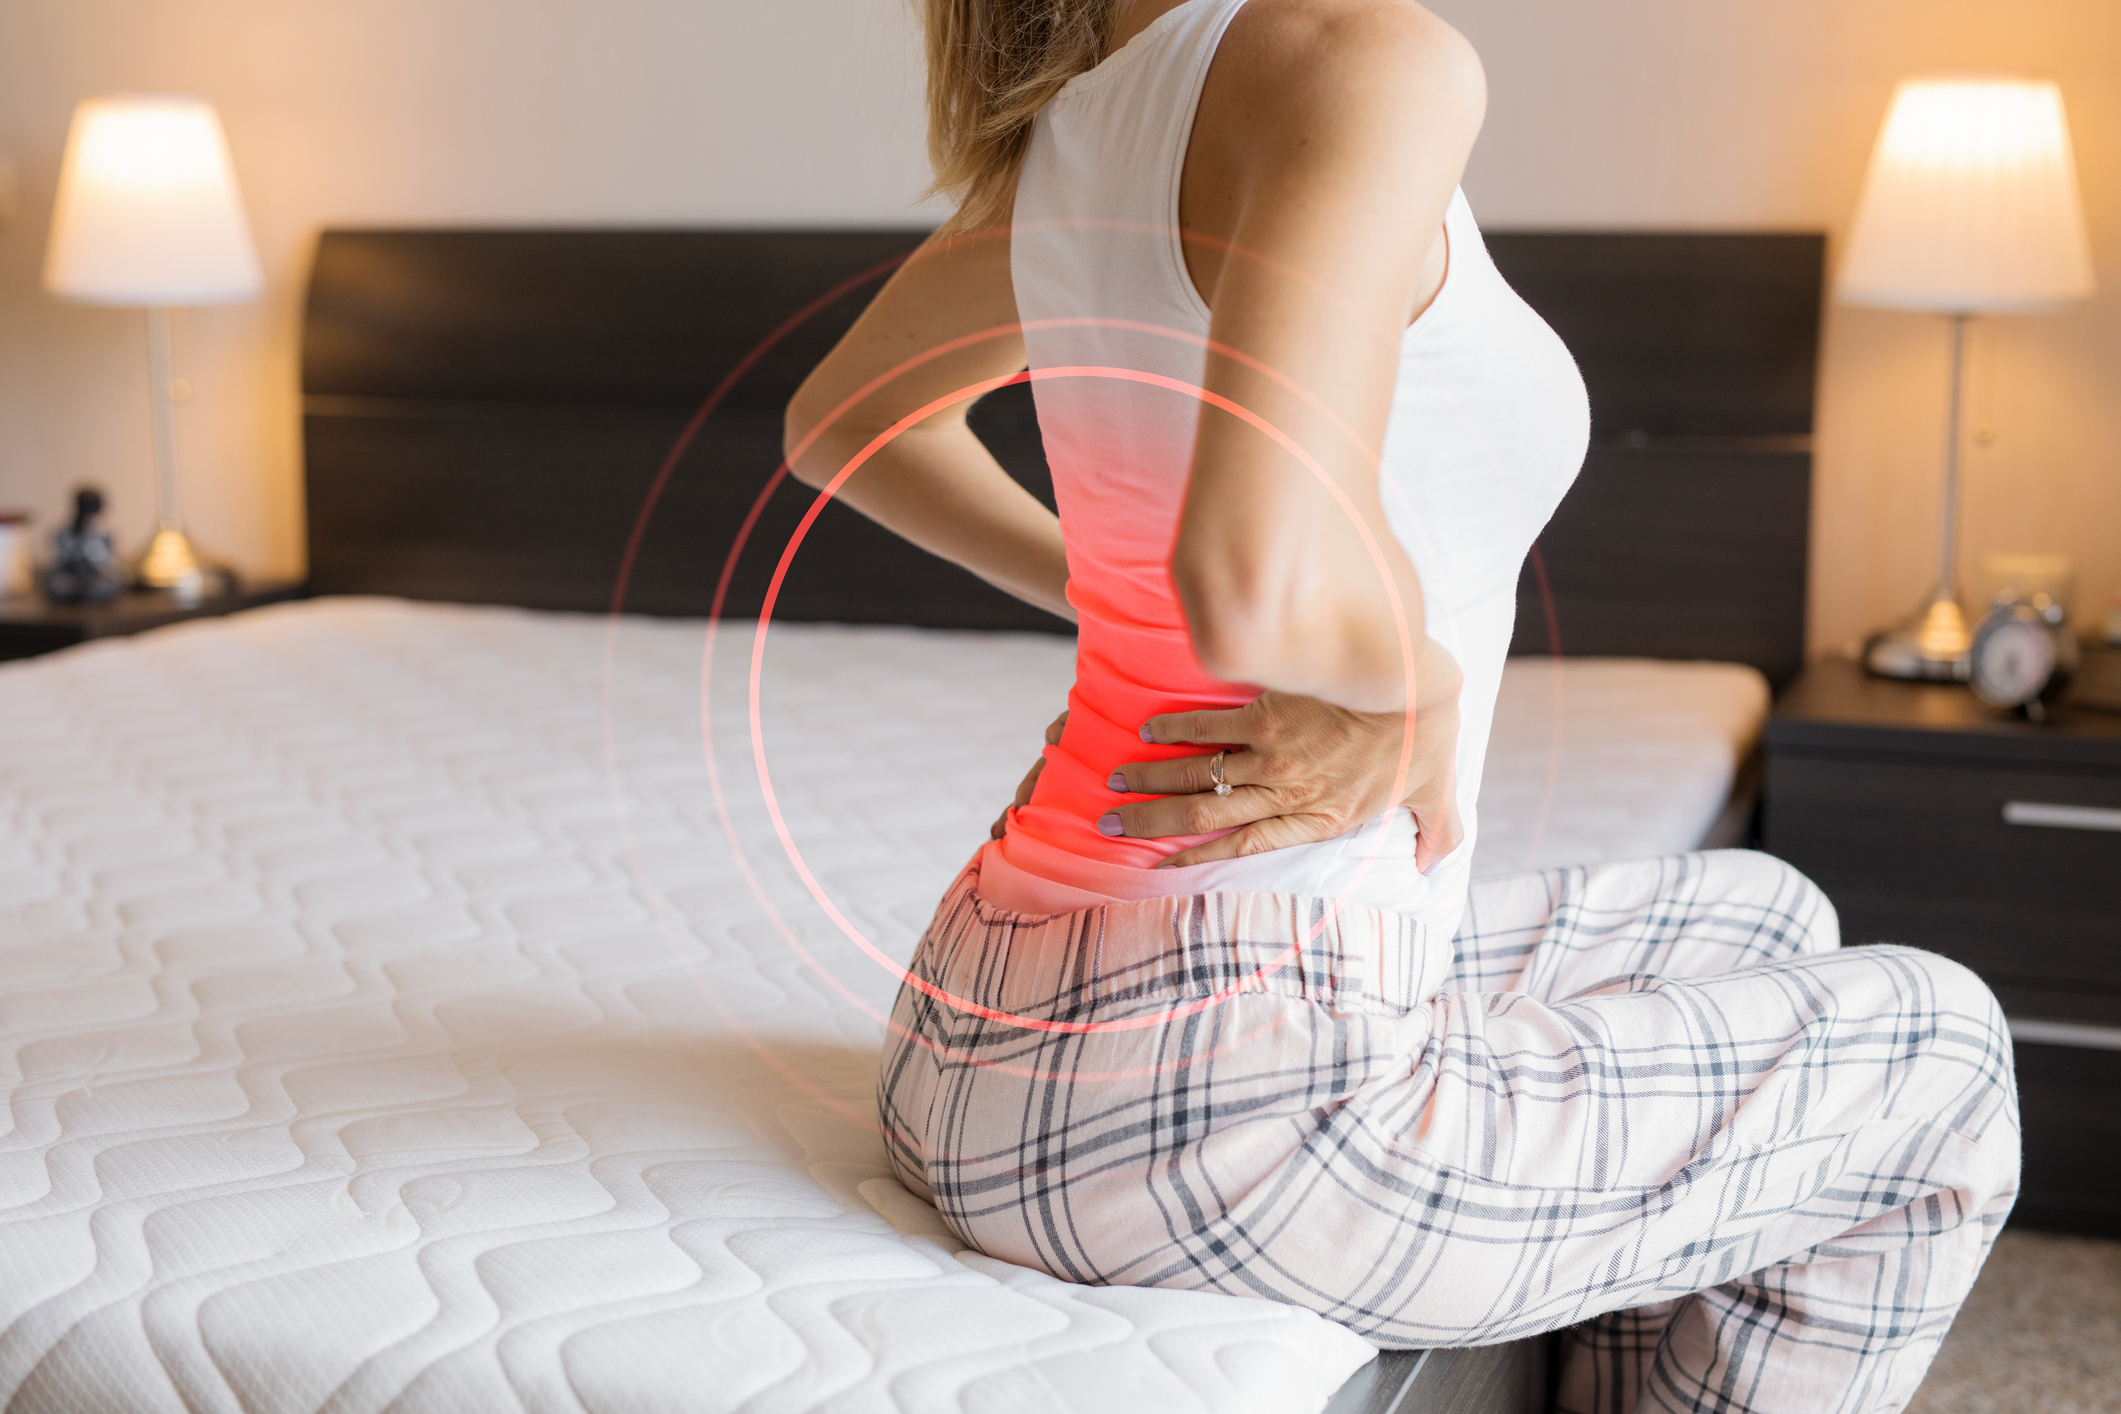

Sore joints can be a significant barrier to exercise. The unprovoked pain you experience each day might make the thought of increasing movement seem like a terrible idea. But it isn’t. Exercise can be extremely valuable for people with joint pain. If it’s done properly. You don’t want exercise to hurt your joints. The idea ...click here to read more